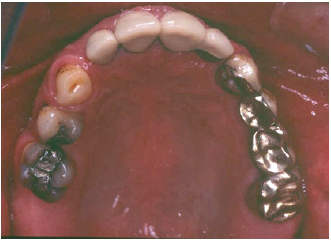

Figure 3: Preoperative occlusal view of the maxilla.

The patient reported a free medical history, but admitted smoking habit (20+cig/day). He was not taking any medication and reported pain in facial muscles during stressful periods. The patient was subjected to thorough clinical and radiographic examination (panoramic x-ray) (Figure 2). Intraorally, he presented severe abrasion most observed in mandibulary dentition, reduced VDO, and several missing mandibular teeth (#44,45,46,47 and 36,37). In the maxilla, a 4-unit metal ceramic bridge with a cantilever was found on the incisors {12-11-21-(22)}, and one 4-unit metal-acrylic bridge in the posterior segment {23-(24)-(26)-27}. The visible diastemmas between #12,#13 and #13,#14 were due to a missing premolar #15 which probably caused distal migration of #14 and 13 (Figure 3-5). The smile line was evaluated as medium (Figure 6). Secondary caries was visible in amalgam restorations in #14 and #16 and was inspected under the abutment #12. A significant change in the occlusal plane was obvious, defined by significant protrusion of #13, #14 and #16. In the mandible acrylic crowns were positioned in #44, 33, 34. Initial radiographic examination revealed endodontic therapies in #12, 34, 35, 42 and #43 and it was estimated that the bone level averaged at 70%. Clinical examination of the stomatognathic system revealed bilateral myalgia of the lateral pterygoid muscles on palpation, unilateral clicking on the left TMJ and limitation in mouth opening. All other masseter muscles were free of symptoms.